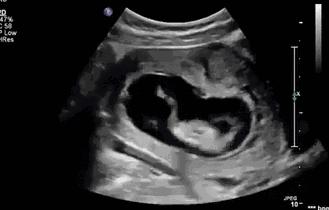

在怀孕到四个月的时候,准妈妈们大多都会感到胎动,后面会越来越明显,变成这种:

“山丘隆起”型